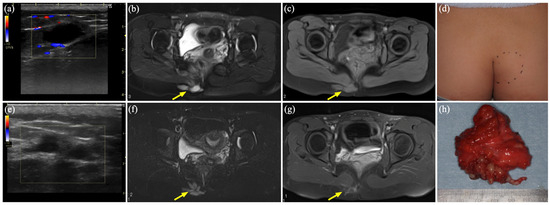

3.3. Case 2

3.4. Case 3

| 2 | 15 | F | Rt buttock | VM | US, MR, CT | Sc, 2 times | Schwannoma | 1186 |

| 3 | 25 | F | Lt head | VM | US, MR | Biopsy | Schwannoma | 37 |